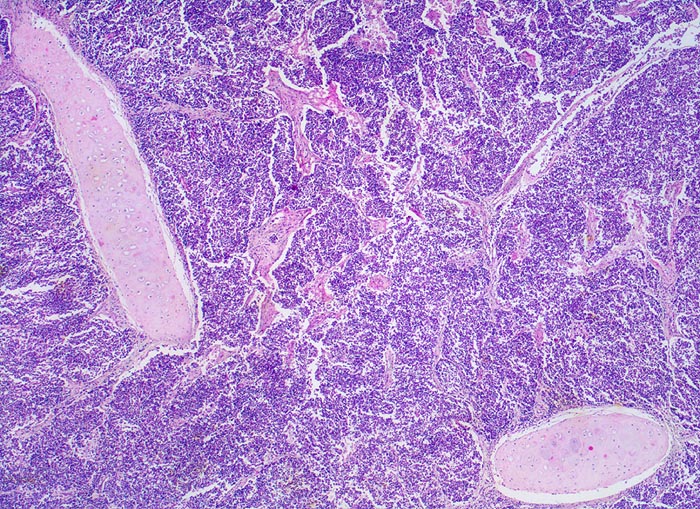

PathoPic – image database / PathoPic ID 4720 - kleinzelliges Bronchuskarzinom

kleinzelliges Bronchuskarzinom

Das Karzinom bildet Stränge, die von schmalen Bindegewebssepten durchzogen werden. Das Tumorgewebe hat einen Segmentbronchus infiltriert und zerstört. Inseln von stehengebliebenem Bronchialknorpel werden vom Tumor umflossen. Aufgrund des hohen Kernanteils ist der Tumor blau gefärbt.

Inoperables metastasierendes Bronchuskarzinom. Nikotinabusus 70 Packyears.